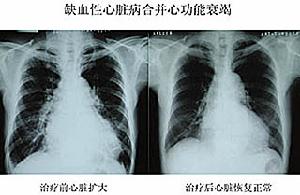

(3)充血性心力衰竭:心臟常呈普遍性擴大,以左室擴大為主,屬於一種收縮功能不全性心衰。75%以上患者表現為左心衰,如咳嗽、陣發性呼吸困難、端坐呼吸及肺部濕囉音;1/3的患者表現為全心衰。部分老年患者心衰的客觀體徵明顯而無自覺症狀,雖然靜息射血分數降低,運動時也不升高但具有相當的運動耐量,這可能是通過增加舒張末期容量和心律、擴大動靜脈差以及增加組織對氧的攝取等代償機制來維持較合適的心輸出量所致。心電圖可見病理性Q波、ST—T缺血性改變及各種心律失常(以室性和/房性早搏、房顫、病態竇房結綜合症、房室傳導阻滯和束支阻滯多見,亦可有陣發性心動過速)。X線示心臟普大型、心臟搏動減弱及肺瘀血。超聲檢查有心臟普大型,以左室為主,室壁變薄,舒張末期溶劑增大,室壁運動呈多個節段性減弱或消失。射血分數降低常<35%,心肌顯象有多節段心肌放射性核素灌注缺損區。冠脈造影有多支病變。